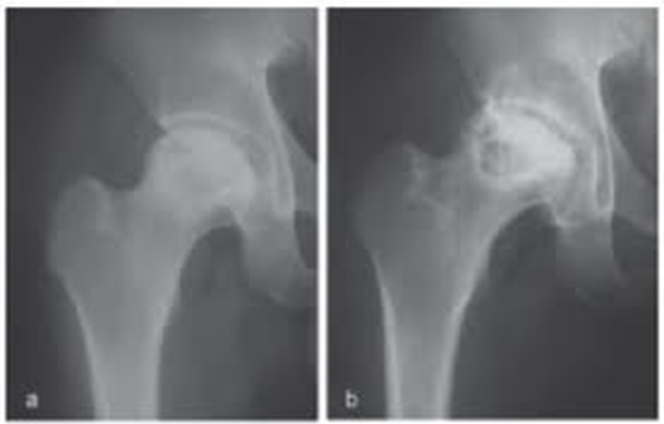

(2)肌肉、关节、骨骼系统:气泡形成于肌肉、关节、骨膜等处,可引起疼痛。关节痛为减压病常见症状,约占病例数的90%。轻者出现酸痛,重者可呈跳动样、针刺样、撕裂样剧痛,迫使患者关节呈半屈曲状态,称“屈肢症(bends)”。骨质内气泡所致远期后果可产生减压性坏死(或称无菌性骨坏死),国外报道有经验的潜水员发病率约为 25%,国内报道为26%,好发于股骨和肱骨上端。

减压性骨坏死

减压性骨坏死的病因与机理主要是由于骨骺血管内氮气泡积聚,产生局部缺血;此外,尚有脂肪栓塞、血小板凝聚、气体引起渗透压改变、自体免疫反应等的综合作用。

②减压性骨坏死

主要根据双肩、双髋和(或)双膝关节及邻近长骨的影像学改变和临床表现分期"

Ⅰ期(早期、无关节塌陷)

无明显临床症状或轻度关节疼痛,关节活动无明显障碍。股骨、肱骨和(或)胫骨影像学机检查具有下列表现之一者:

a) X射线检查:见局部的骨致密区、致密斑片影、条纹影或小囊变透亮区,后者坏死灶被硬化带包裹;

b) CT检查:见轮廓清晰的坏死灶或囊变透亮区;

c) MRI检查:T1加权像(T1WI)呈带状低信号、T2加权像(T2WI)包围骨坏死灶低信号带内侧出现高信号带,呈双线征或囊变表现;T2WI抑脂:坏死灶周缘高信号带。

Ⅱ期(中期、关节塌陷前期)

中度关节疼痛,关节活动轻度受限。无明显障碍。具有下列表现之一者:

X射线显示:骨改变面积,上肢或下肢达到或超过

a) X射线检查:股骨或肱骨头外轮廓中断,新月征阳性;或出现大片骨髓钙化;

b) CT检查:关节软骨下骨折,新月形坏死区;

c) MRI检查:新月形坏死区;T1WI带状低信号、T2WI抑脂示骨髓水肿征象。

Ⅲ期(晚期、关节塌陷期)

重度关节疼痛,关节活动明显受限,关节畸形。X射线片示病变累及关节,肱骨或股骨头塌陷、变形,关节间隙变窄,髋臼或肩关节盂破坏或硬化,严重者出现骨关节炎表现。